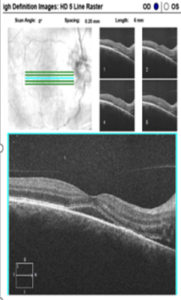

![]() Figure 2B. HD OCT 5-line raster scan of the right macula showed serous macular detachment with areas of hyper-reflectivity in the inner sensory retinal layers. Click to enlarge |

Humphrey visual field central 30-2 threshold testing of the right and left eye was clear and reliable. Optical coherence tomography (OCT) of the peripapillary retinal nerve fiber layer showed significant thickening temporally consistent with the clinical appearance of optic disc edema (Figure 2A). OCT also confirmed the presence of serous macular detachment with scattered areas of hyper-reflectivity along the inner retinal layers (Figure 2B). B-scan ultrasonography of the optic disc was unremarkable for buried drusen of the optic nerve in the right and left eye.